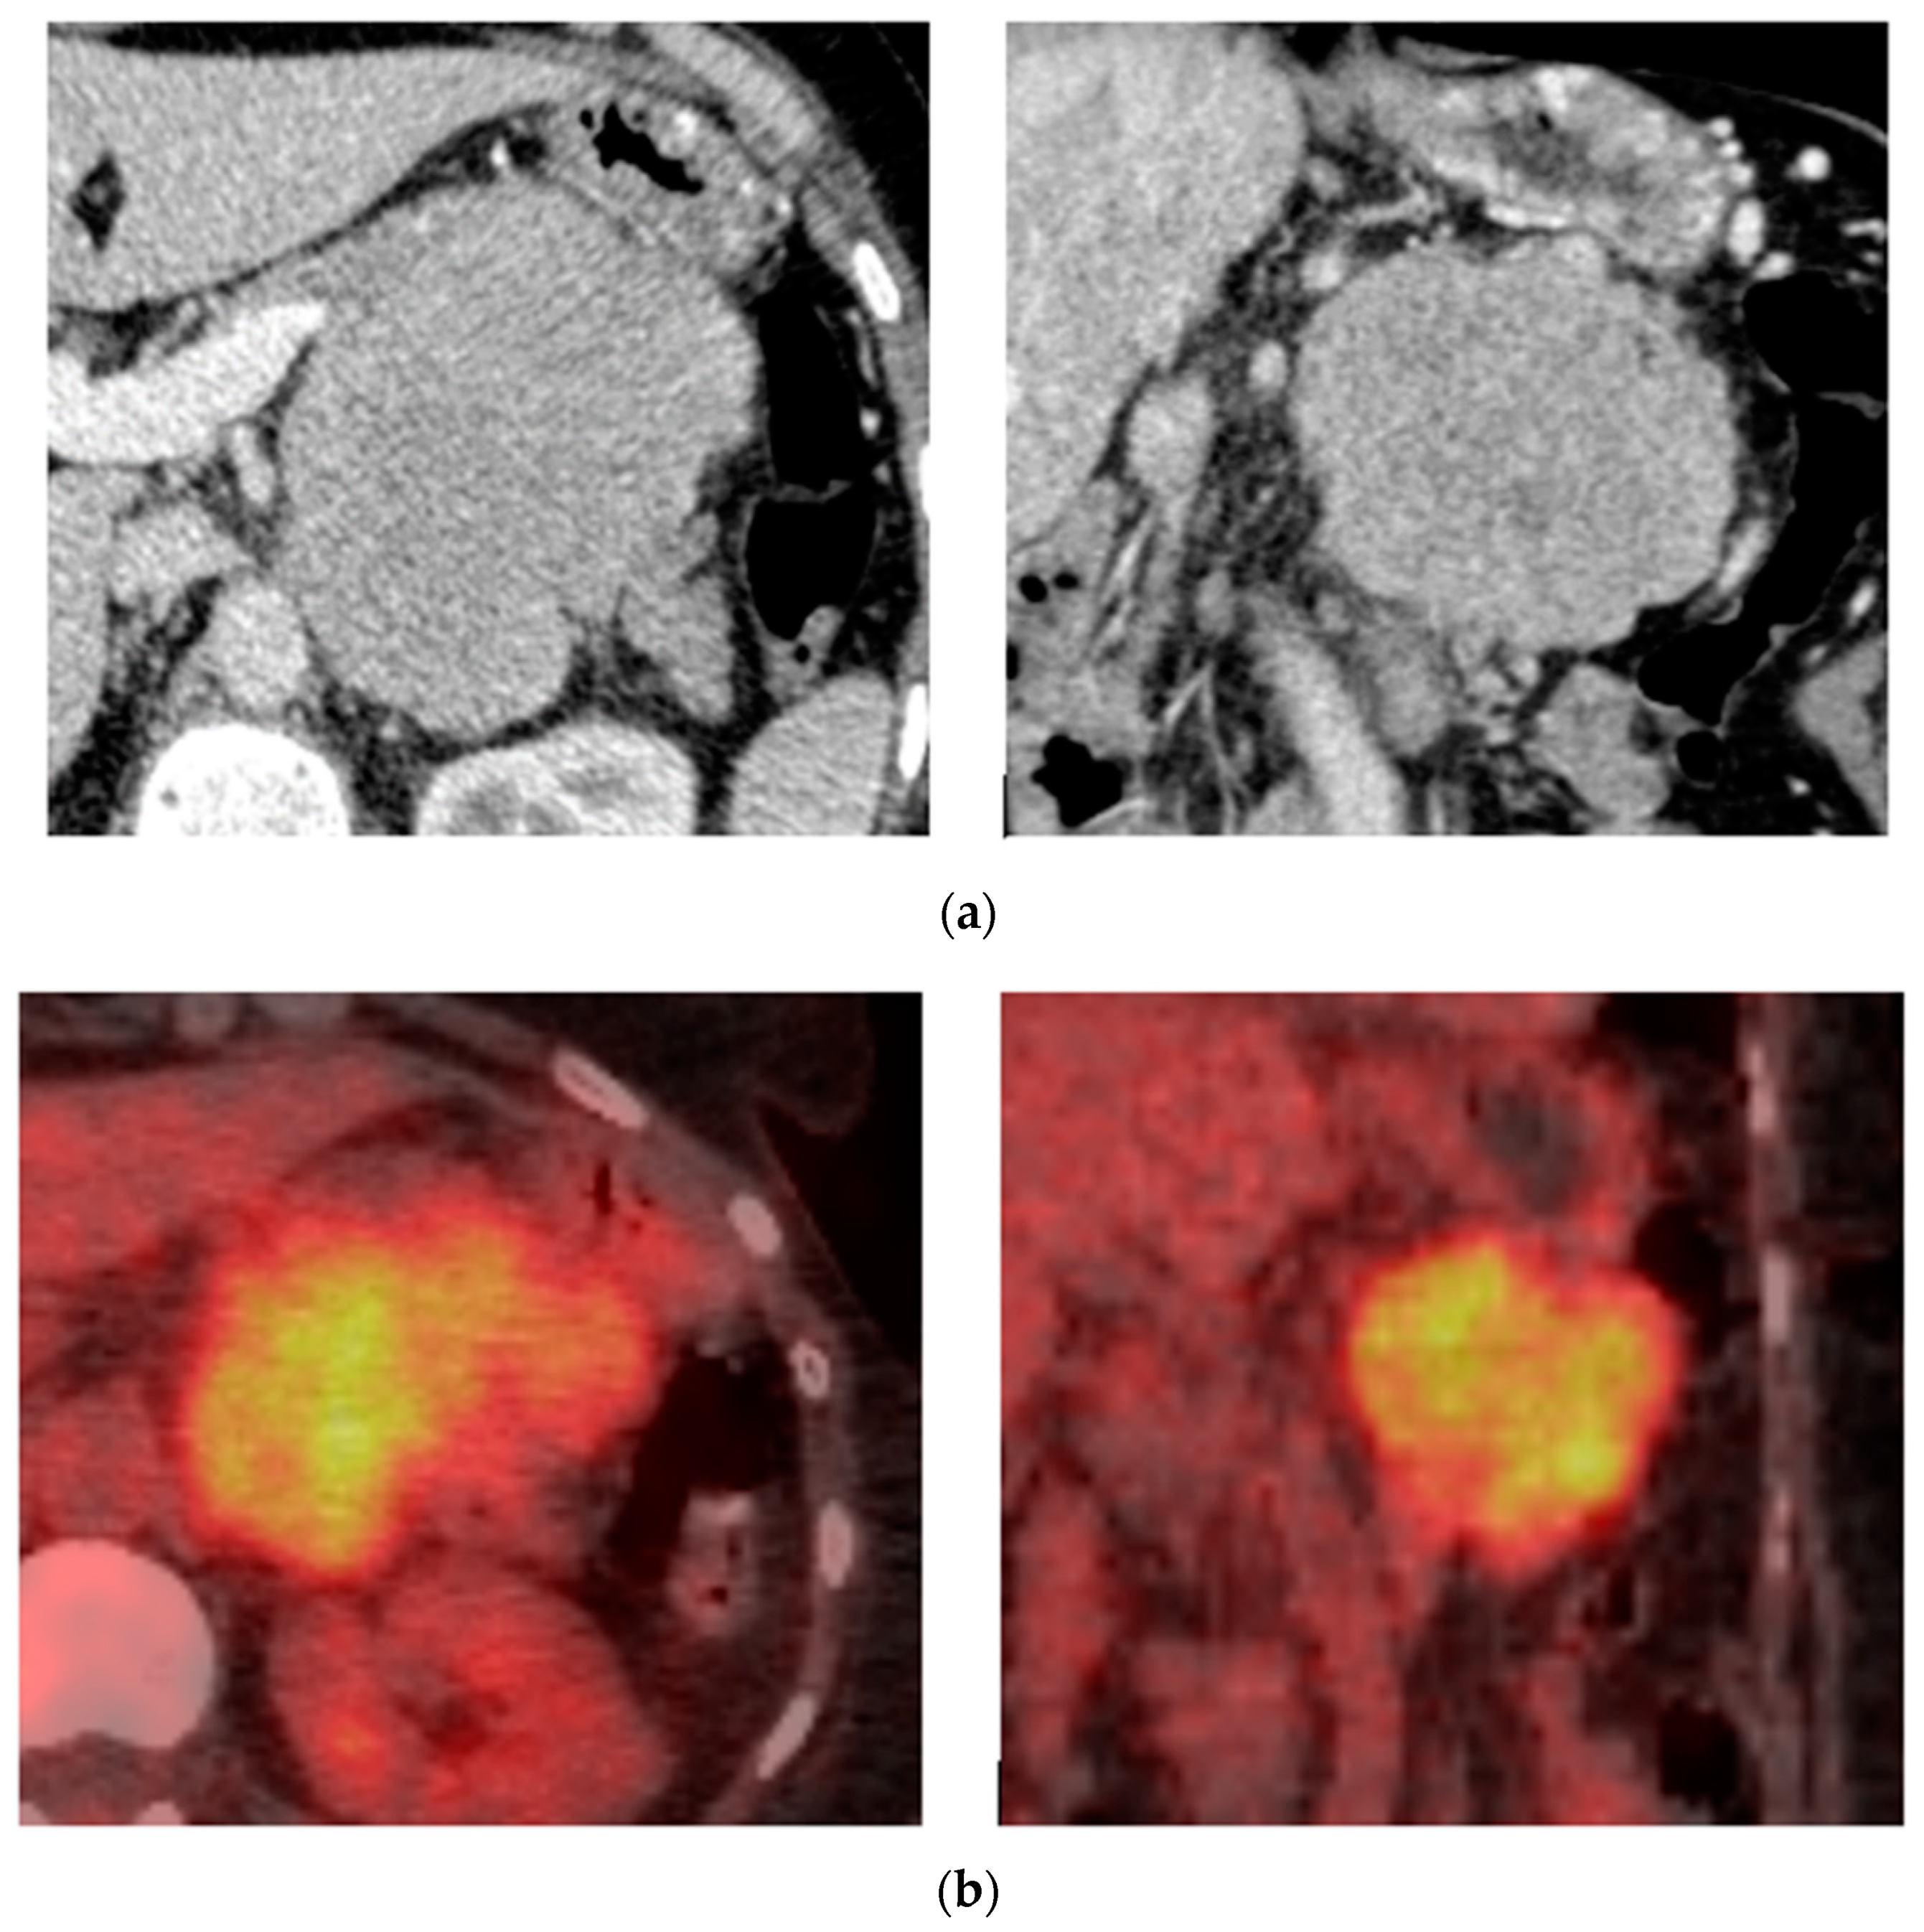

9. Renal